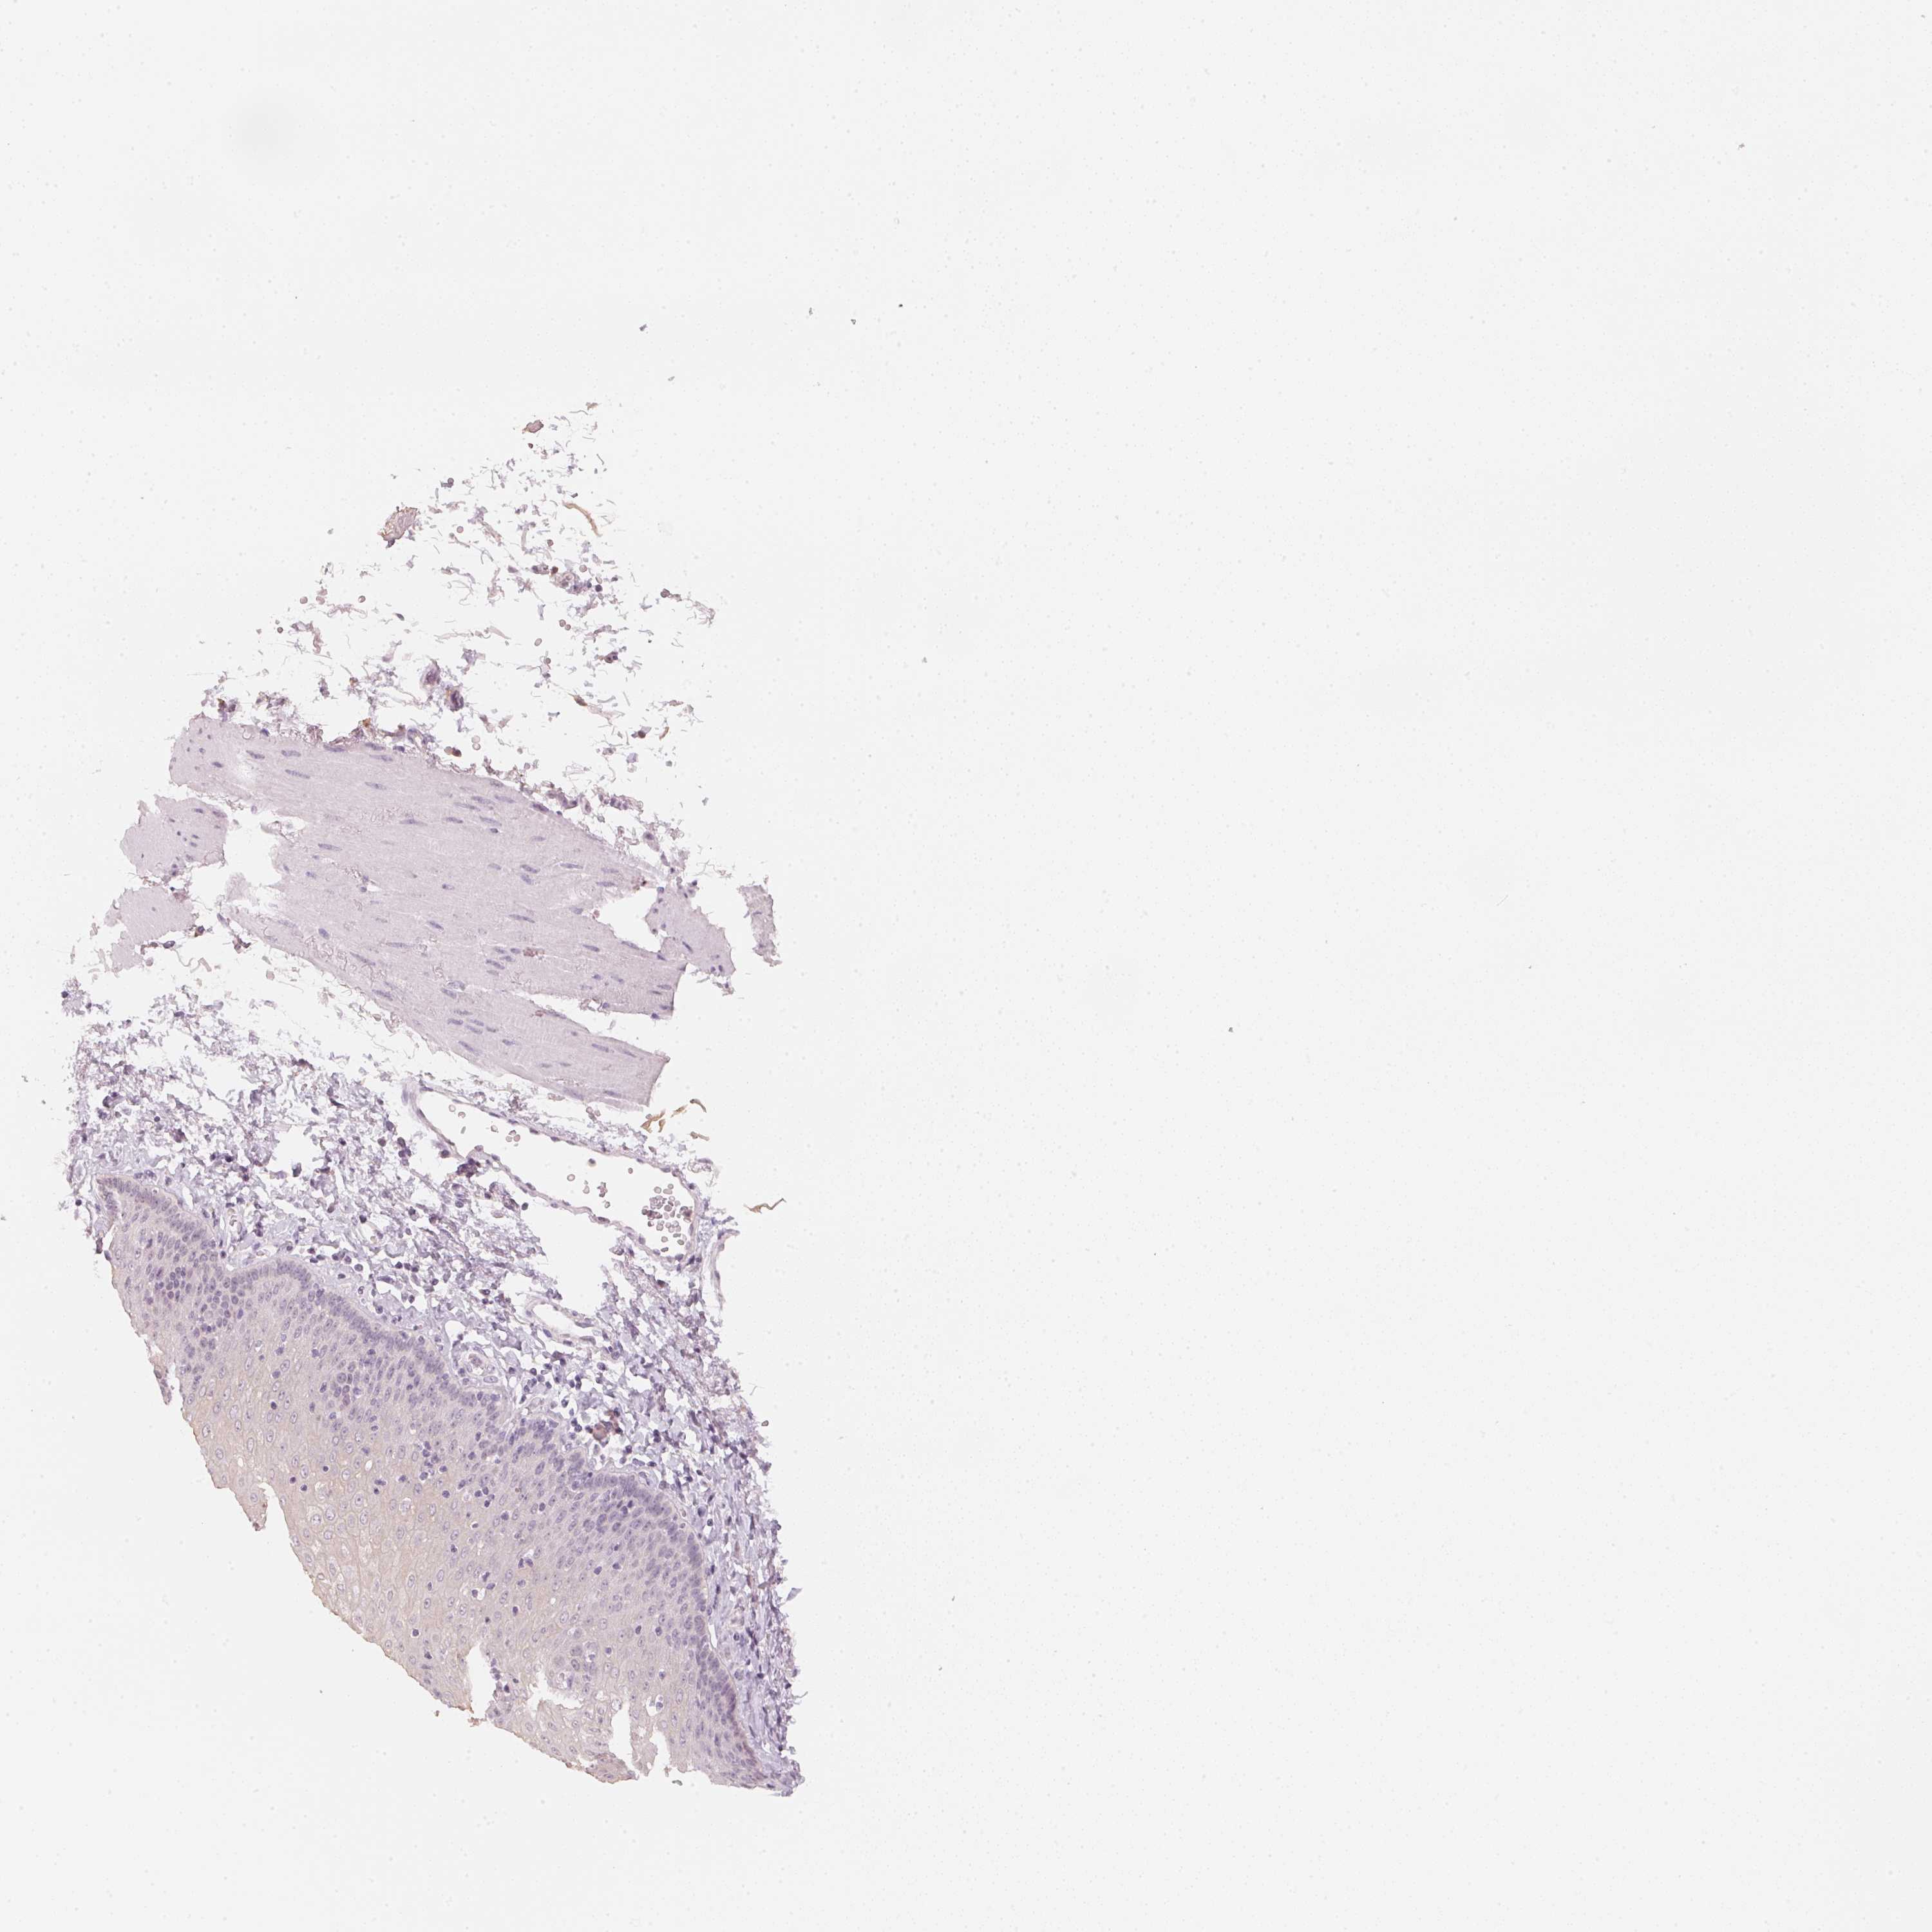

ESOPHAGUS - Antibody stainingi

Antibody staining in the annotated cell types in the current human tissue is reported as not detected, low, medium, or high, based on conventional immunohistochemistry profiling in selected tissues. This score is based on the combination of the staining intensity and fraction of stained cells.

Each image is clickable and will lead to virtual microscopy that enables deeper exploration of all samples and also displays staining intensity scores, fraction scores and subcellular localization as well as patient and tissue information for each sample.

Antibody HPA049684

Squamous epithelial cells Not detected